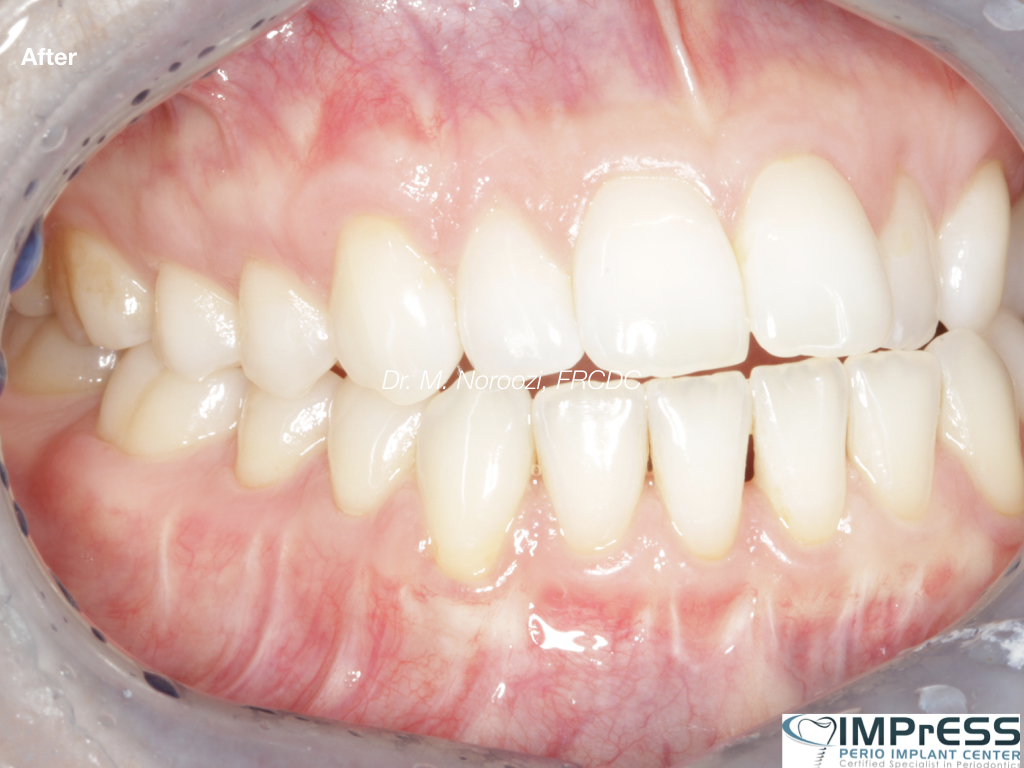

Connective Tissue Gingival Grafting for Gingival Recession